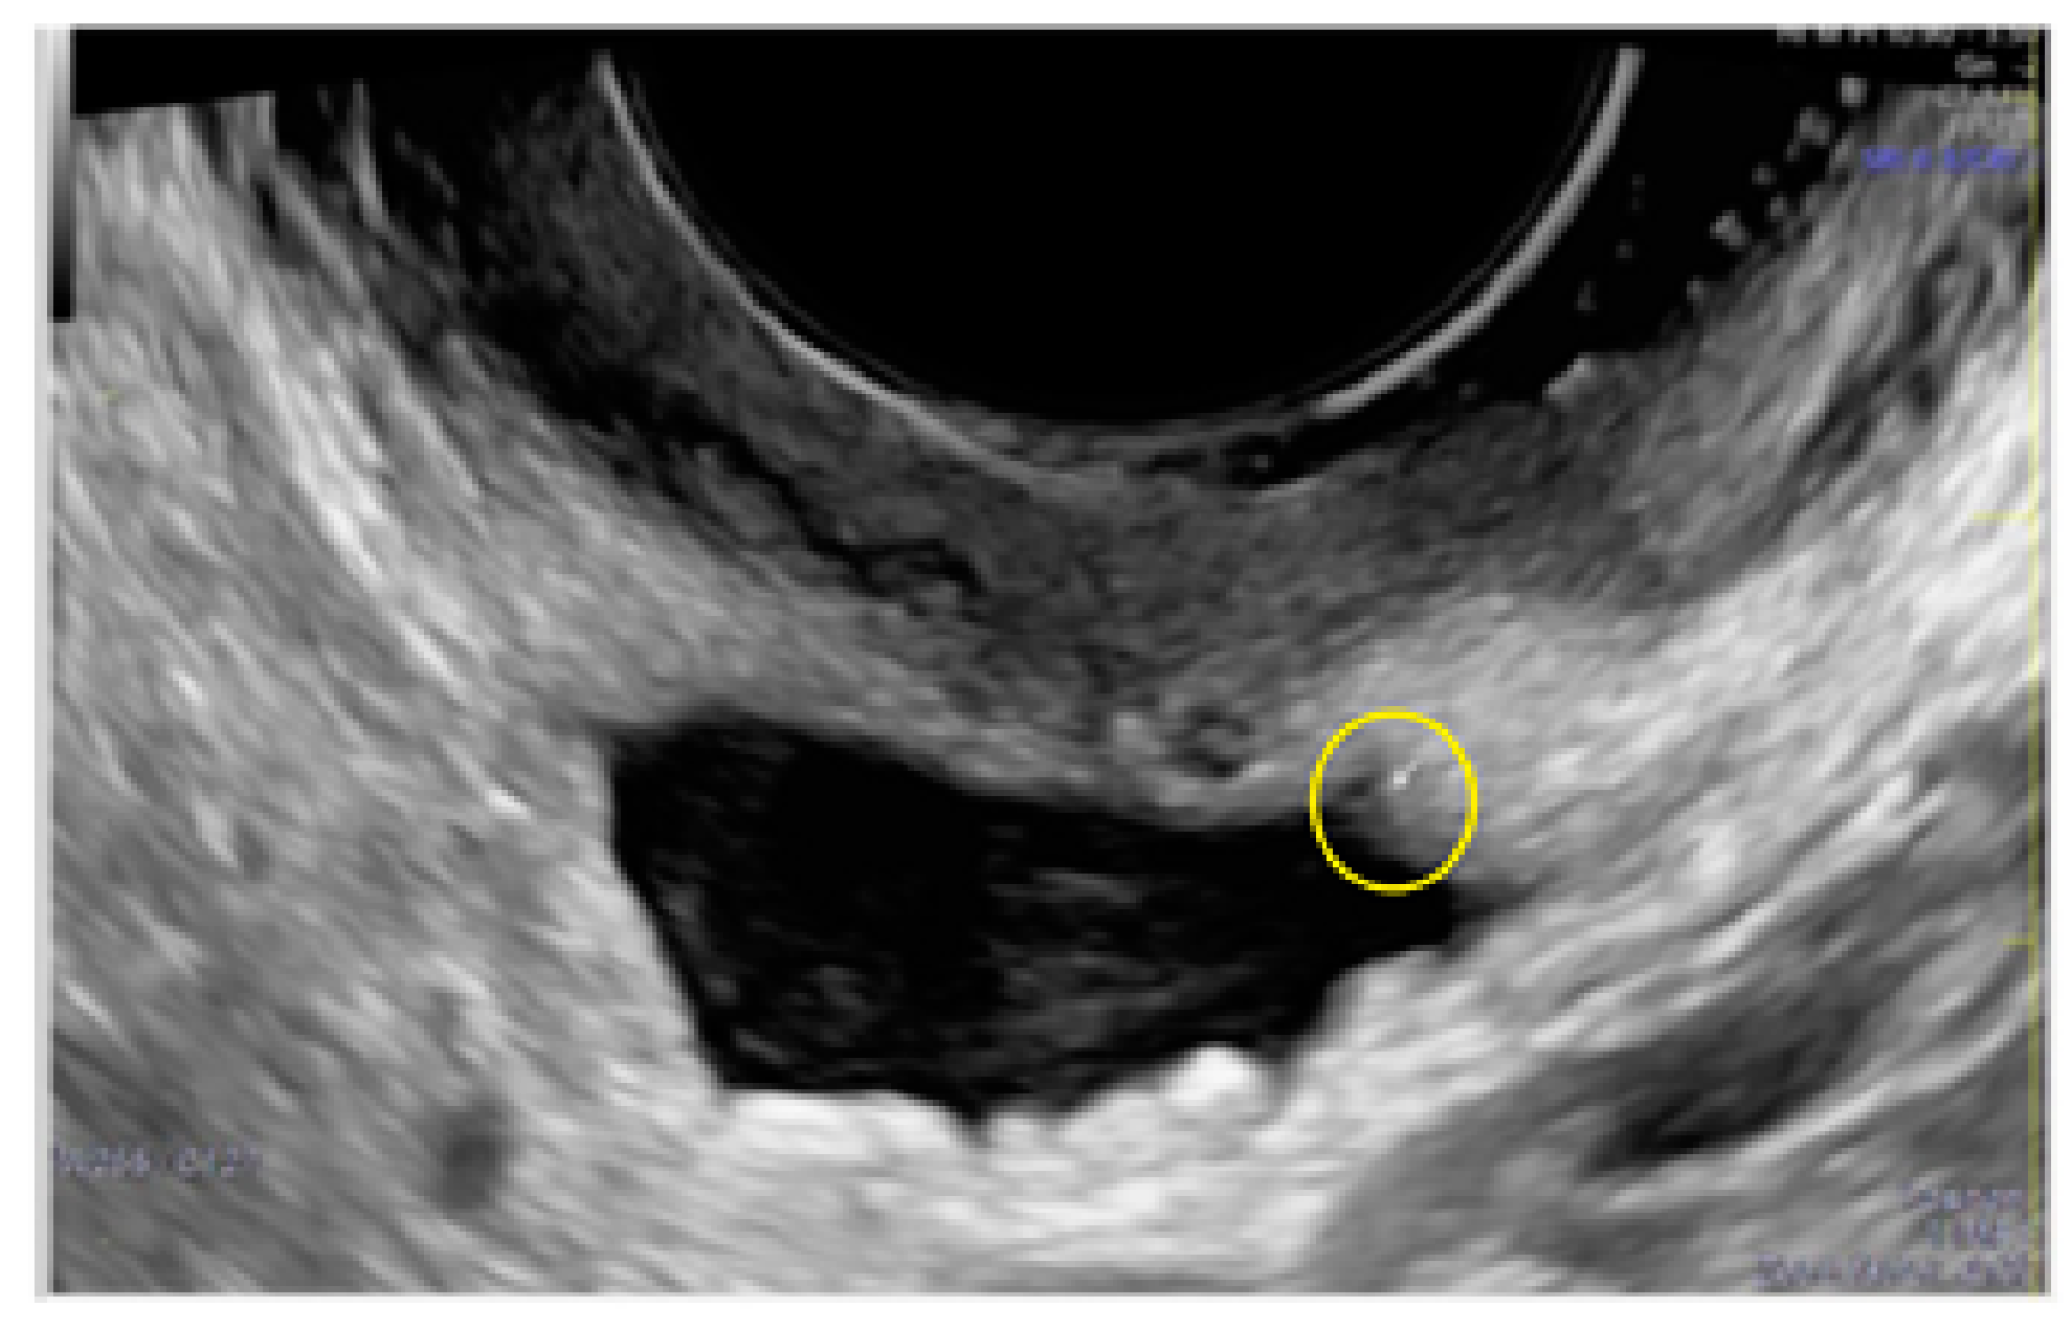

- The presence of hypoechogenic associated tissue (hypoechoic areas surrounding a small cyst area; we called this a “hat”). This tissue does not protrude or invaginate the peritoneal surface.

3.3. Cystic Lesions Arranged in a Cluster